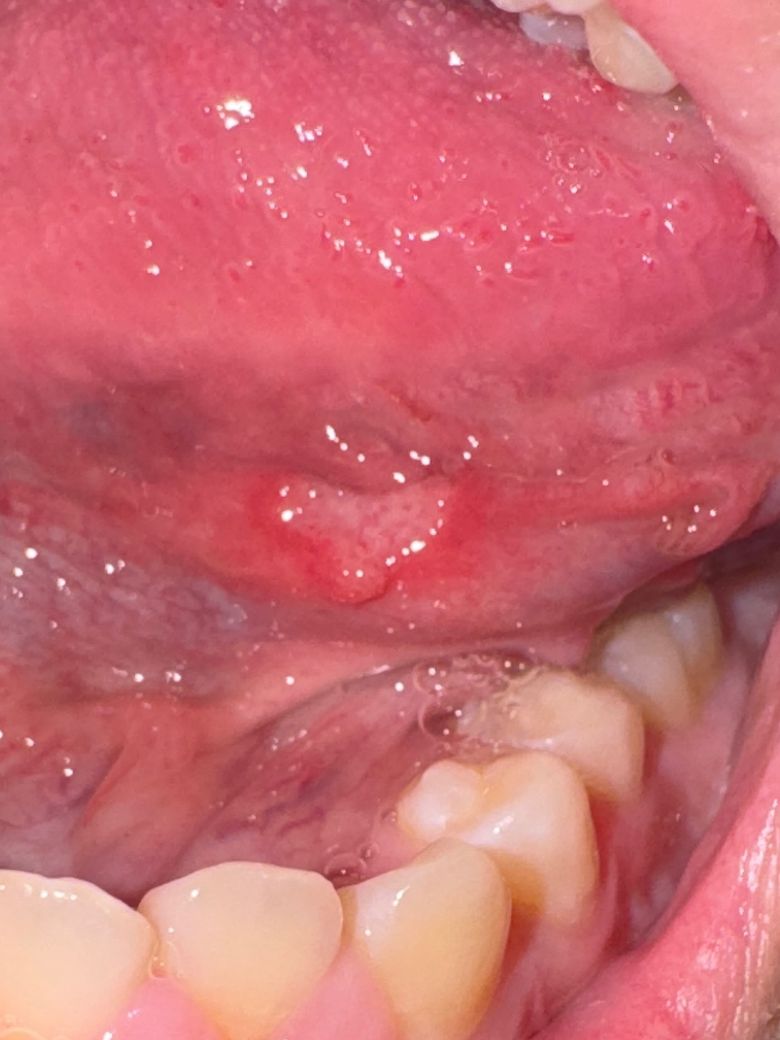

너무 아프고 구내염처럼 동그란?게 아니고

제가 많이 마는 구내염처럼 좀 정직한 동그라미가 아니고

저런 모양인데 다른병은 아니겠죠... ㅠㅠㅠㅠ

가장 가능성이 높은건 구냐염이긴 합니다만 1~2주내 호전되지 않고 병소가 더 커진다면 구강내과가보세요